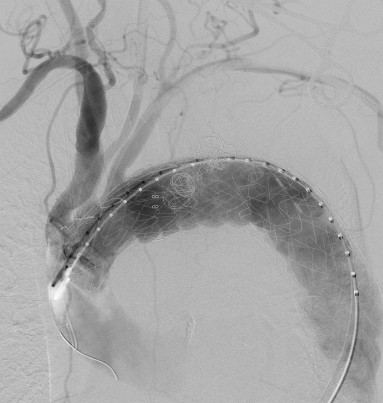

穿刺股動(dòng)脈、切開頸動(dòng)脈、肱動(dòng)脈建立入路,超選內(nèi)漏口、栓塞瘤腔,體外預(yù)開窗、重建弓上動(dòng)脈......血管外科兩組人馬同時(shí)開工,有條不紊。在麻醉科林芩主任團(tuán)隊(duì)的密切配合下,一系列步驟緊張有序地進(jìn)行著。手術(shù)持續(xù)了4個(gè)多小時(shí),當(dāng)最終的造影確認(rèn)內(nèi)漏完全封閉、假性動(dòng)脈瘤成功隔絕,并且主動(dòng)脈弓上的重要分支動(dòng)脈血供良好的那一刻,血管外科團(tuán)隊(duì)成員都已忘卻了身上幾十斤的鉛衣和滿身的汗水。夏印主任和黎成金主任不禁對(duì)視一笑:“拆雷成功,又救了一條命?!?

左頸總動(dòng)脈、鎖骨下動(dòng)脈雙開窗

瘤腔及內(nèi)漏成功封堵,弓上分支動(dòng)脈血流通暢